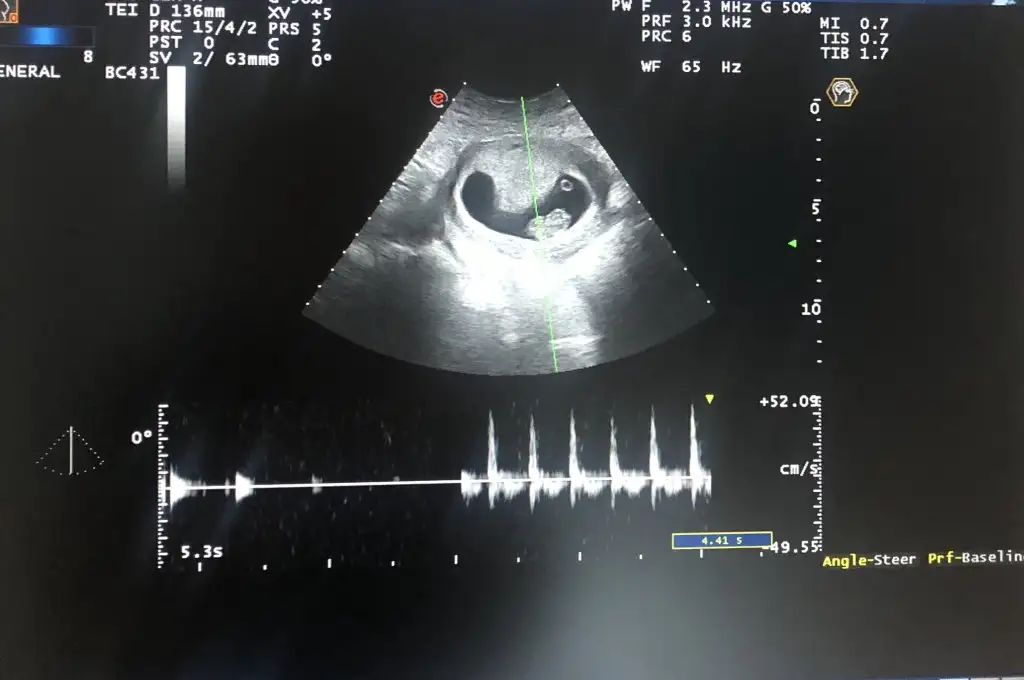

Pekiii bende ne dersin ?

Üstteki 9 haftalik diger ikisi 7 haftalik, ve vaginal ultrason :)